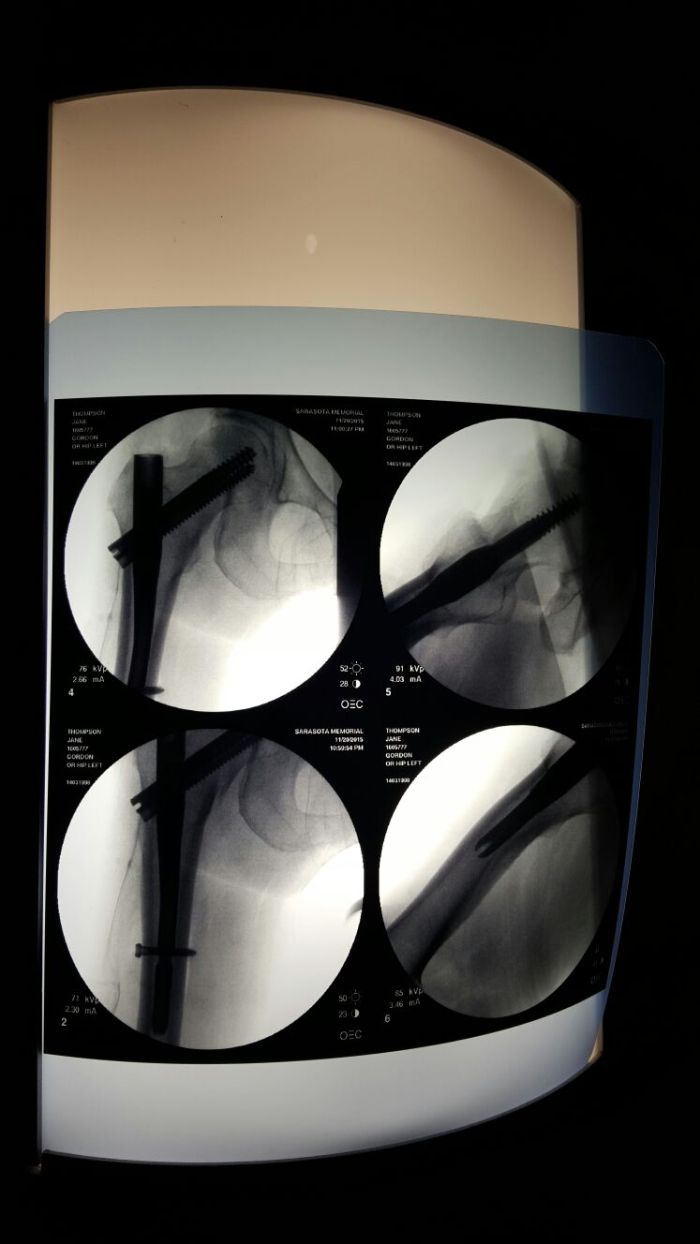

Then pain came roaring back. After months of tests and no answers, I saw a hip specialist. He said it never healed. The ball is collapsing. Bipolar hip replacement surgery is scheduled for November. I’m back to managing pain and walking with a cane.